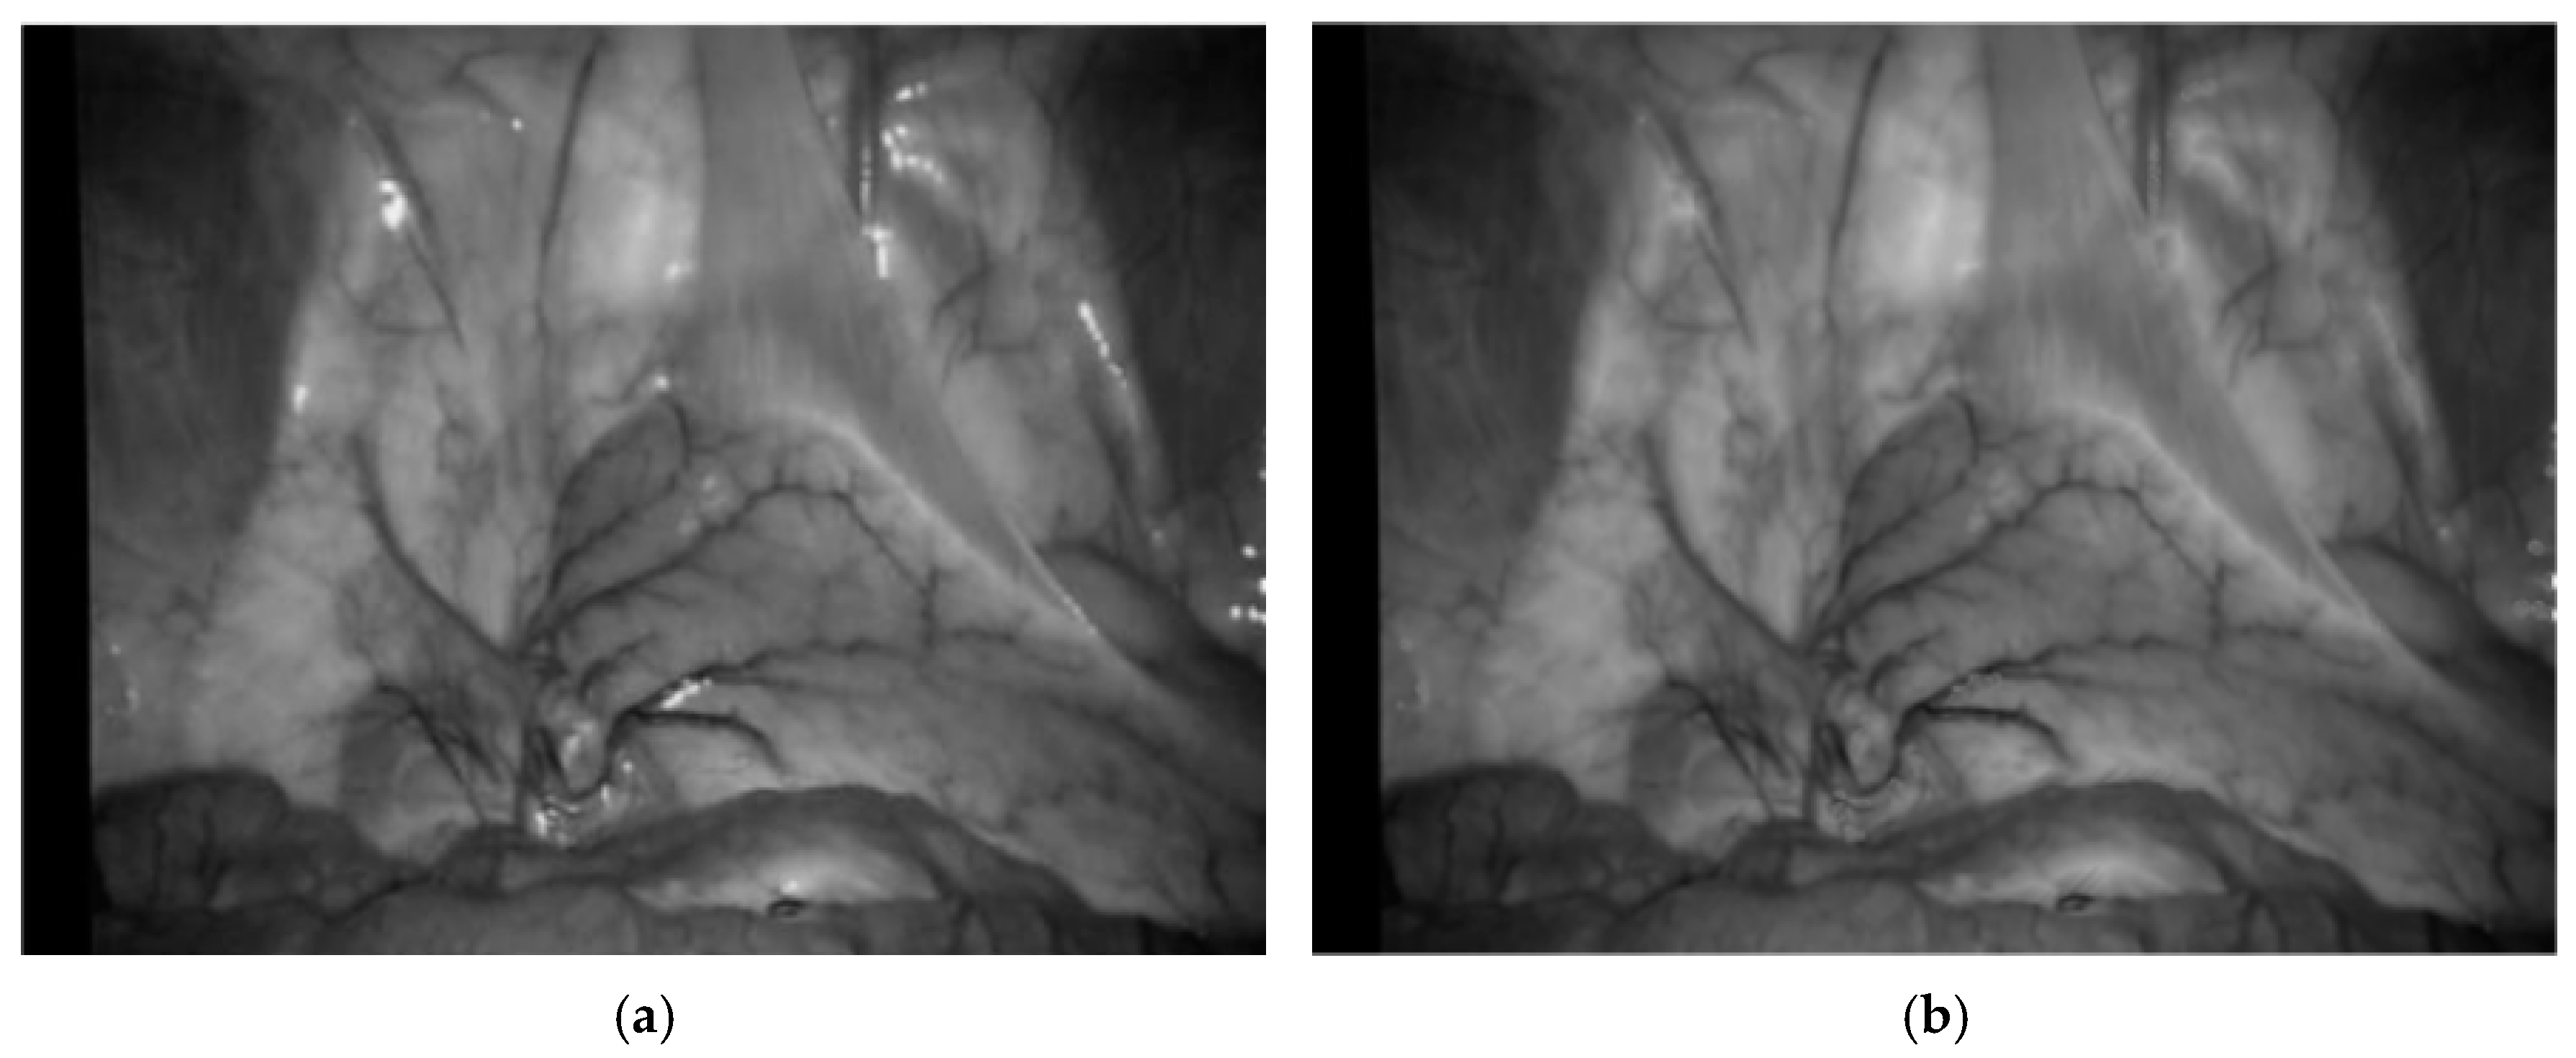

where Iridge represents ridge degree. As shown in Figure 6, (a) is the enhancement result of the Frangi enhancement method, and (b) is enhancement result of this paper method. The blood vessels after single-pixel transformation are thinner and have clearer branches compared to the original method blood vessel images in the human lumen.

Figure 6.

Enhancement results of vascular structure enhancement: (a) the Frangi enhancement method; (b) the method proposed in this paper.